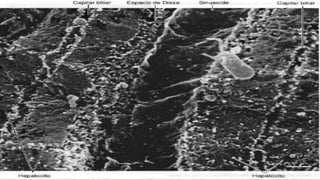

• Parénquima: cordones de hepatocitos.

• Estroma de Tejido Conjuntivo: Capsula

de Glisson, vasos, nervios

• Sinusoides. (células de Kupffer)

• Espacios perisinusoidales (Disse).

(células de ito= esteres de retinol,

miofibroblastos)

Sinusoides

• Fenestraciones grandes.

• Brechas amplias

• Celulas de Kupffer

• Espacios de Disse.